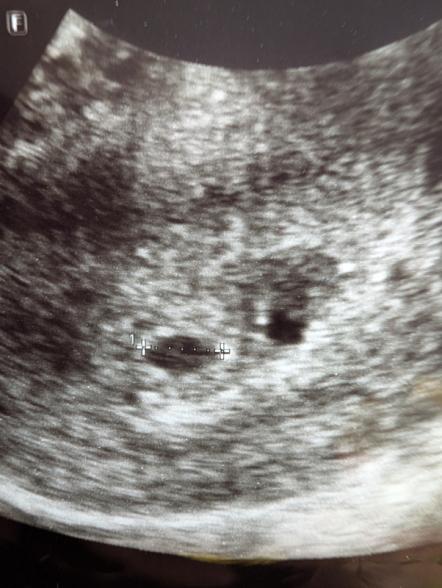

妊娠5週頃のエコー写真についてご相談です。

診察していただいた先生からは5mmで

順調に育っているとのお話のみでしたが

エコー写真を見返した際、測定した黒丸の右横にも

同じような黒丸がありこれはなんなのかと心配になりました。

胎嚢の近くにもう一つ黒い点が見られるのですね。実際にエコーを拝見していませんので、はっきりとしたことは明言できませんが、可能性として考えられるのは、出血のこともありますし、粘膜の塊などがそのように見えることもあります。また、おっしゃるように、双子の可能性もあると思います。

ですが、医師からは特に何も指摘がなかったということであれば、出血や双子ではない可能性が高いように思いますよ。粘膜の塊などが黒っぽく見えることもありますので、何も言われていないのであれば、そのようなものなのかもしれませんね。

結果「水分か何かが映り込んでいるだけで心配するものではないですよ」との回答をいただきました。特に問題がなかったのでその場でも説明を省かれていたようです。